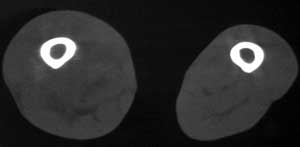

标题: CT4055:骨肉瘤?

男56涨疼5-6月

右股骨下端包绕股骨见巨大软组织肿块,密度部俊,周围见瘤骨,下端骨皮质侵蚀变薄,骨质周围无骨膜反应, 考虑右股骨软骨肉瘤。

右股骨下段周围软组织肿块伴钙化,相邻股骨骨皮质受累,考虑软组织来源恶性病变

右股骨下段骨肉瘤,软组织内瘤骨,软组织肿块。